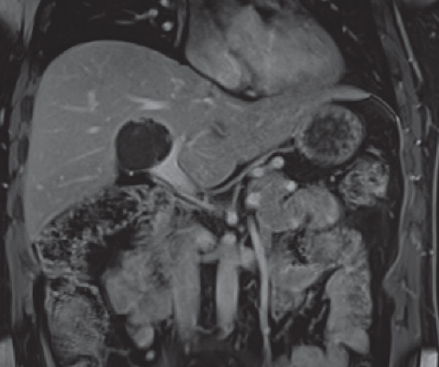

Introducción: Los schwannomas de la vía biliar corresponden a una entidad extremadamente infrecuente, habiéndose reportado solo escasos casos en la literatura. Casos Clínico: El presente paciente corresponde a un hombre de 45 años, a quien durante examen rutinario se le pesquisa una lesión quística hepática. La resonancia magnética confirmó la lesión, y la biopsia de la pieza resecada diagnosticó la existencia de un Schwannoma benigno con marcadores positivos para vimentina y proteína S-100.